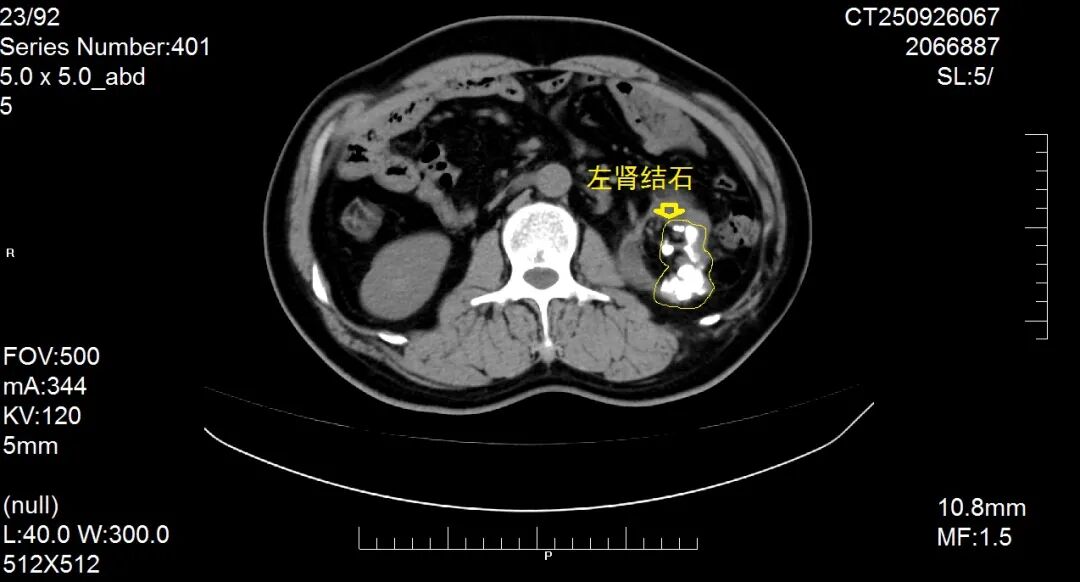

患者因“反复肉眼血尿1月,再发加重1周”入院,经系统检查确诊为复杂性肾结石

该患者结石体积大、负荷高,且合并肾内结构变异,常规微创治疗难度极高。科室团队经全面评估后,决定另辟蹊径,摒弃微创手术需反复多次取石的不足,采用传统的开放肾盂肾实质切开取石术。